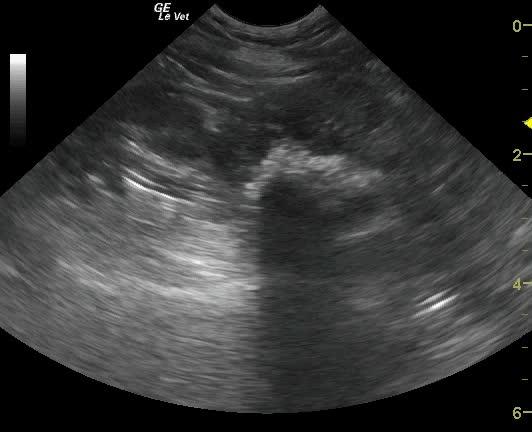

A 15-year-old NM West Highland White terrier dog was presented for evaluation of polydipsia, polyuria and possible bladder stones noted on radiographs. Abnormalities on CBC and serum biochemistry were thrombocytosis, neutrophilia, and hyperalbuminemia. Urinalysis was not performed owing to financial constraints however an abdominal ultrasound prescription was approved.